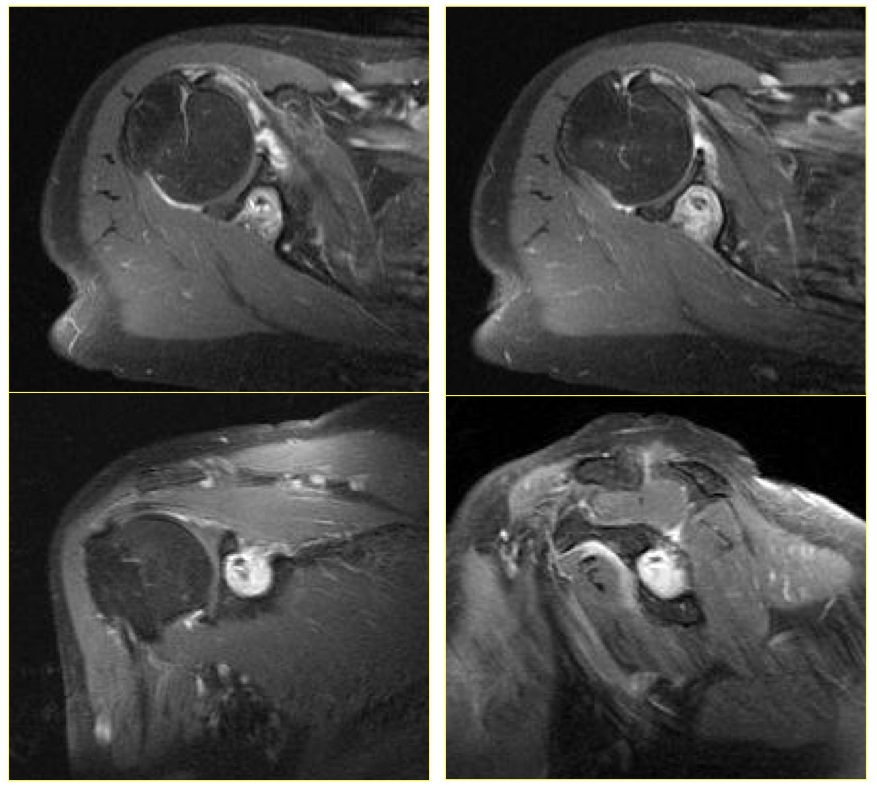

Inflammatory Myofibroblastic Tumor; WHO classify inflammatory myofibroblastic tumor as a distinct borderline lesion with uncertainty as to whether it is reactive or neoplastic; characterized histologically by the presence of acute and chronic inflammatory cells with a variable fibrous response

inflammatory pseudotumor ( RID3860 )